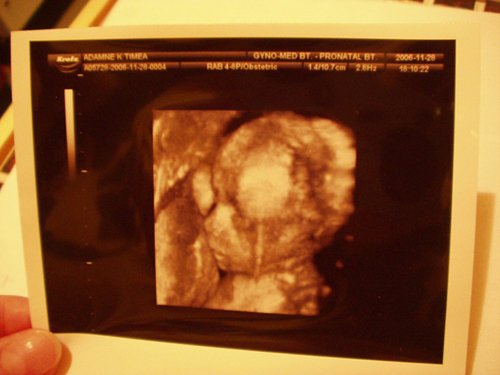

Mazsola: üdv itt megint köztünk! Gratula a babához! Én a második terhességemmel pont 25hetesen voltam 4D-n uh-n, de mivel nekem nagy volt a picurom, ezért nem lehetett egészben látni, csak részletekben, hogy éppen mit csinál a kislányom.

de igy is nagyon jó volt, most neked hány cm-t, és hány kg-ot saccolnak az uh-n?

Ha elvileg olyan súlyú mint az átlag babák, amiket irnak, hogy mennyi kell legyen a 25.héten, akkor szépen fogod látni, ha nagyobb, akkor már nem fér bele a képernyőbe teljesen, csak részletekben, mint a lányom.